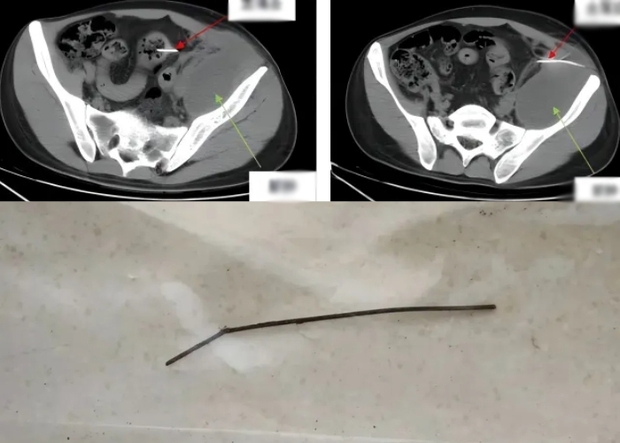

Hình ảnh chụp CT ổ bụng và dị vật kim loại dài 13cm đã được lấy ra khỏi ổ bụng bệnh nhân (Ảnh bệnh viện cung cấp)

Ông kể lại: “Qua phim chụp thấy dị vật có có hình dáng dẹt, chiều ngang nhỏ nhưng một đầu nhọn, cứng, không bị đứt gãy và dài tới 13cm. Dị vật đã xuyên qua ruột, xuyên vào thành bụng, tạo thành một mụn mủ lớn ở sau phúc mạc, lan sang hố chậu nên cần phẫu thuật ngay”.

Bác sĩ Cao Yanbing cho biết, ca phẫu thuật của Tiểu Thiện kéo dài 2 giờ 40 phút bằng phương pháp nội soi. “Chúng tôi thật sự bất ngờ khi phát hiện dị vật là một xiên que bằng kim loại dài 13cm, chuyên dùng để xiên thịt nướng tại các quán ăn hay nhà hàng. Que kim loại đã xuyên qua thành ruột đại tràng sigma và xuyên vào phúc mạc bên trái, có dấu hiệu rỉ sét. Sau khi lấy được dị vật ra ngoài, chúng tôi tiến hành xử lý áp xe phúc mạc và hố chậu, lấy ra khoảng 180ml mủ đen xám có mùi hôi thối sau đó làm sạch và xử lý tiếp các vết thủng ruột” - ông nói chi tiết hơn.